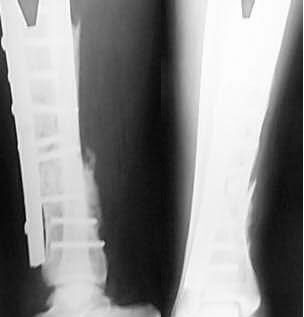

32 year old manual labourer sustainal closed fracture lower 1/3rd Tibia in June 2001 and was treated elsewhere. Today he comes to me with painful limping. Clinically there is local tenderness and mobility at fracture site. Serial Xrays are attached.

(Sorry for the poor Quality of last Xray taken today which shows Broken screws. Please suggest further management.

From: William Obremsky

The alignment looks good in the AP and lateral views, and the fx appears to be trying to heal w/ posterior callus. Why did it not heal? Does he smoke?, Big dissection and soft tissus stripping w/ this big plate? Too early weight bearing? I would vote for giving it a chance to heal in cast or protected weight bearing before complete failure occurs.